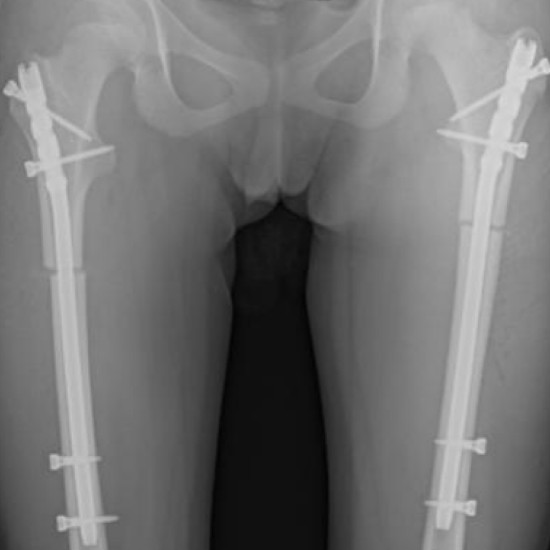

The nail features a design that accommodates a lateral entry site through the greater trochanter. It has an anatomic shape and is made of titanium, being a cannulated nail suitable for both reamed and unreamed techniques.

The nail is available in lengths ranging from 240 mm to 400 mm, in 20 mm increments. It is specifically designed for patients in whom Titanium Elastic Nails are not large enough, and the Lateral Femoral Nail for adults is too large. The nail comes in 8.2 mm, 9 mm, and 10 mm diameters, all with a proximal end diameter of 11 mm.